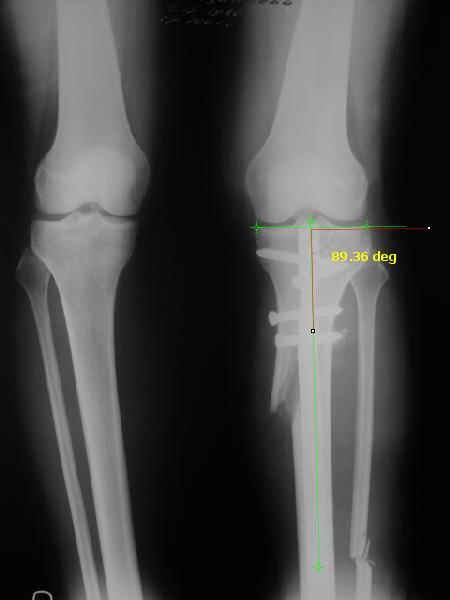

I am attaching a word doc with a 'print screen' of the program in use, showing the images being viewed and analysed

. On the right leg you can see some of the tools (from the tool bar above) applied to demonstrate a mild mech-axis varus of about 5 degrees.

On the left the bone landmarks used in the anlaysis are shown.

The data for the analysis are in the XLs sheet below, exported from the program automatically.

I have given a label of the abreviations and some normative values.

In essence she has a mild mech-axis varus of 7 degrees with some contribution from the femur (2) degrees and more from the tibia (6 degrees), none from the joint.

The analysis took about 6 mins.

Regards

Derek

TDVC> In essence she has a mild mech-axis varus of 7 degrees

TDVC> with some contribution from the femur (2) degrees and more from

TDVC> the tibia (6 degrees), none from the joint.